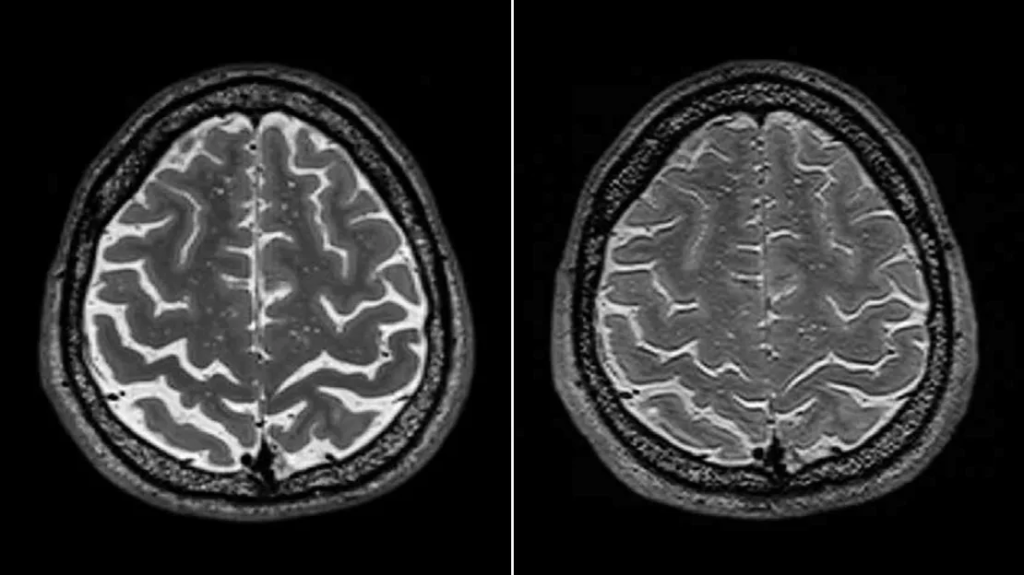

Due to the lack of gravity, cerebrospinal fluid (CSF) flows to the top of the body, thus making the brain float slightly higher in the skull. Additionally, since the cerebrospinal fluid flows up the body, it causes the expansion of cerebral ventricles (spaces in the middle of the brain containing CSF). The expansion of vertebral ventricles can squish surrounding brain tissue (as seen in the below image). In fact, age-related cerebral ventricular expansion has been attributed to cognitive decline.